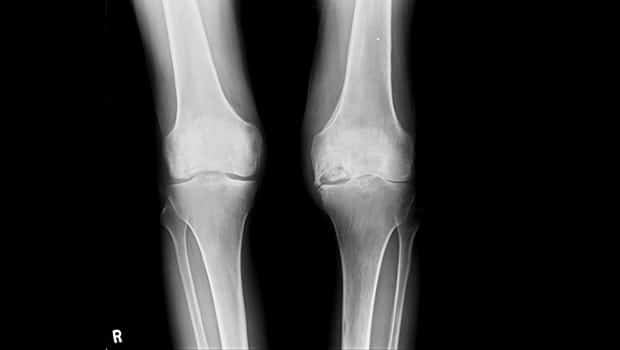

درد ناشی از نکروز آواسکولار ممکن است در کشاله ران، ران یا باسن احساس شود. علاوه بر این قسمتهای دیگری مانند شانه، زانو، دست و پا ممکن است تحت تاثیر آن قرار بگیرد. گاهی برخی از افرادی که دچار نکروز آواسکولار هستند، بهصورت دو طرفه این بیماری را تجربه میکنند، بهعنوان مثال دو طرف لگن یا دو طرف زانو.

رادیوگرافی یا X-ray معمولاً اولین قدم تشخیصی است و میتواند تغییرات ساختاری استخوان را در مراحل پیشرفته نشان دهد. با این حال، MRI دقیقترین روش برای تشخیص نکروز آواسکولار در مراحل اولیه محسوب میشود، زیرا امکان بررسی جریان خون و بافت استخوان را فراهم میکند. در برخی موارد، سیتیاسکن برای بررسی جزئیات استخوان و برنامهریزی جراحی مورد استفاده قرار میگیرد.